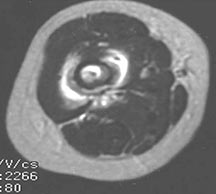

- May arise from any bone and any site within a bone (epiphyseal, metaphyseal, diaphyseal)

- Radiographically variable appearance: may appear benign (geographic) or malignant (permeative or moth eaten)

- Pain and soft tissue swelling